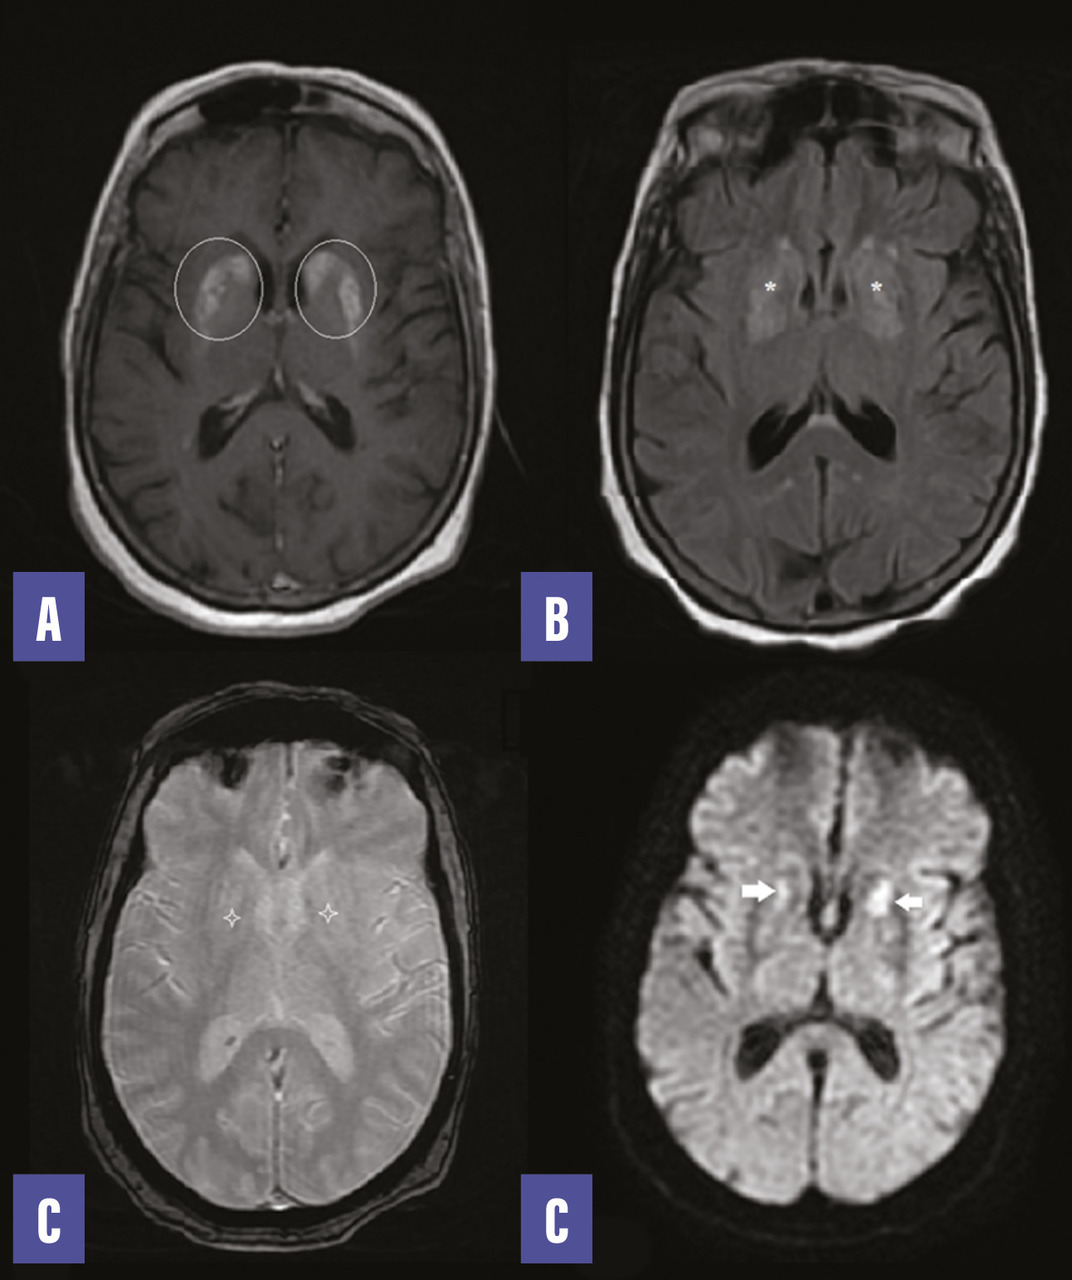

Le bilan biologique révèle une glycémie à 4,1 g/L, une HbA1C à 13 %, un taux de globules blancs à 5 000/mm3, une protéine C-réactive à 5 mg/L. L’ionogramme et la bandelette urinaire sont sans particularité. L’IRM encéphalique montre des anomalies (figure ). Devant cet aspect, le diagnostic d’une striatopathie diabétique est retenu. Un traitement par halopéridol n’a pas permis de nette amélioration des symptômes.

Le bilan biologique révèle une glycémie à 4,1 g/L, une HbA1C à 13 %, un taux de globules blancs à 5 000/mm3, une protéine C-réactive à 5 mg/L. L’ionogramme et la bandelette urinaire sont sans particularité. L’IRM encéphalique montre des anomalies (

Le diagnostic est retenu devant un faisceau d’arguments cliniques, biologiques et radiologiques, sur un terrain de diabète de type 2, compliqué d’une hyperglycémie sans cétose ; le tableau clinique est constitué d’un hémiballisme et d’une hémichorée sans autre contexte neurologique ou toxique. L’imagerie retrouve typiquement une anomalie unilatérale de signal des noyaux gris centraux, en particulier du striatum (noyau caudé et putamen) dans 90 % des cas. Cependant, le signal en T2 et en diffusion peut varier selon le mécanisme d’atteinte ainsi que le caractère uni- ou bilatéral et la localisation de l’atteinte des noyaux de la base.1,2